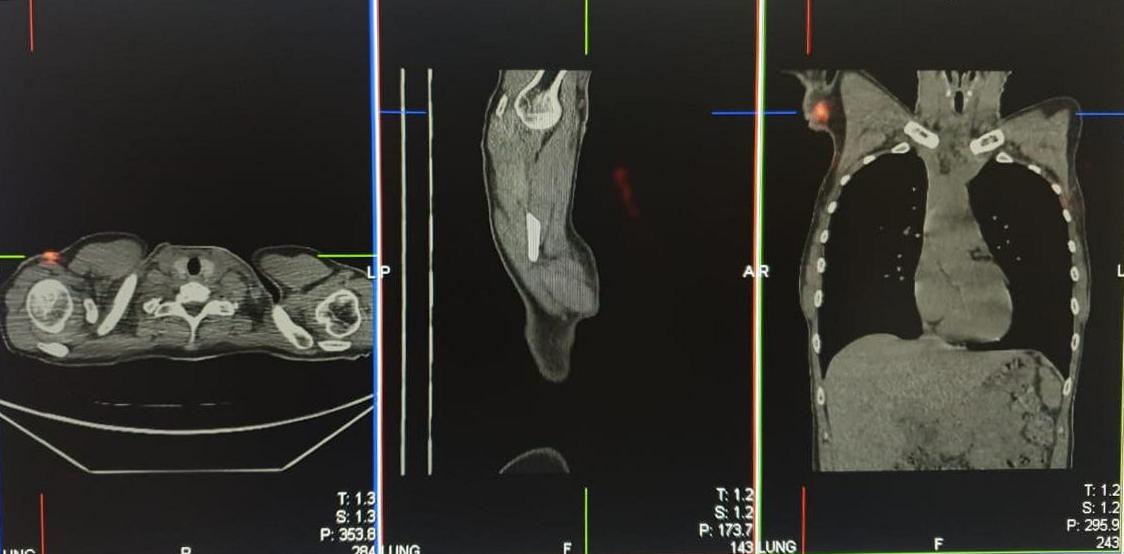

Применяемый при сцинтиграфии сигнальных лимфоузлов радиофармпрепарат «99mTc-Технефит» используется также для сцинтиграфии печени и селезенки, а также лимфосцинтиграфии верхних и нижних конечностей. Это коллоидный препарат, в котором в качестве метки используется радиоактивный изотоп Технеция-99m. В состав радиофармпрепарата входят коллоидные частицы очень маленького диаметра, это позволяет использовать его для сцинтиграфии сигнальных лимфатических узлов. Выполняется внутрикожное, подкожное или перитуморальное (в паренхиму пораженной молочной железы) введение, после чего меченные изотопом коллоидные частички по лимфатическим сосудам проникают в лимфатические узлы и там оседают. Первый лимфатический узел, накапливающий радиофармпрепарат на пути лимфатического оттока от опухоли молочной железы, и является сигнальным или сторожевым.

Данные сцинтиграфии и ОФЭКТ (однофотонной эмиссионной компьютерной томографии) сторожевых лимфатических узлов |

«Сторожевой лимфоузел, который самым первым захватывает меченные радиоизотопом коллоидные частицы на пути лимфооттока от опухоли молочной железы, также первым встречает метастатические опухолевые клетки. Этот лимфатический узел удаляют при интраоперационной биопсии сигнальных лимфоузлов. А далее, пока идет операция, удаленный материал отправляют на исследование с предварительным измерением его радиоактивности (она, как правило, ниже минимально значимого уровня, что позволяет передать его в патологоанатомическое отделение)», — комментирует заведующий отделением радиологии Центра Алмазова к.м.н. Ольга Васильевна Юдина.